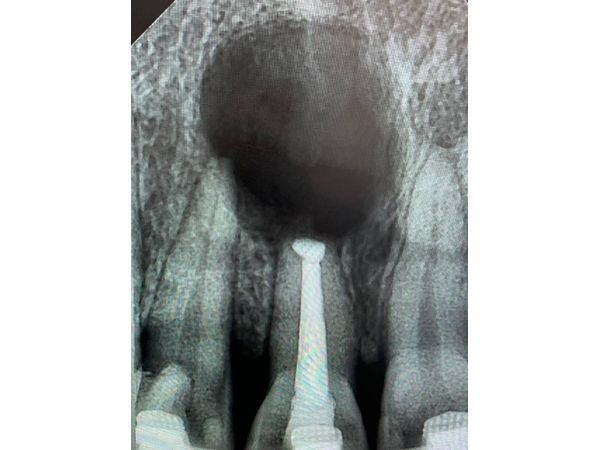

КТ на верхушке корня показала округлое образование диаметром 12,07 мм и немного пломбировочного материала за апексом (местом, где канал соприкасается с твёрдой верхушкой). Сам канал запломбирован хорошо (без дефектов, нерв удалён полностью).

Симптоматический апикальный периодонтит (радикулярная киста).